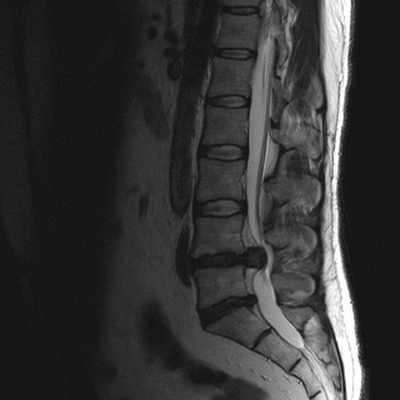

МРТ позвоночника. Сагиттальная Т2-взвешенная МРТ, срединный срез поясничного отдела. Показана нумерация позвонков, измерения позвоночного канала (черная линия). Т- дуральный мешок с ярким ликвором. L- желтая связка. Sacrum - крестец. D - межпозвоночный диск. Голубым выделен остистый отросток, желтым - тело позвонка, Голубые точки - ход корешков.

МРТ позвоночника. Парасагиттальная (околосрединная) Т2-взвешенная МРТ поясничного отдела. Красными стрелками показаны корешки.